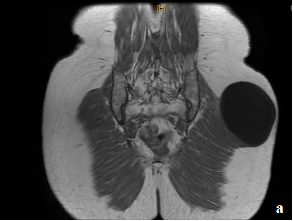

Hydatid cyst of the gluteal muscle: a case report and literature review

Soukaina Adadi, Rabii Isaka Amidou, Zina Lebbar, Hayat Ben Saghroune, Hamza Lakdim, Abdelmajid Elmrini, Zineb Tlamçani